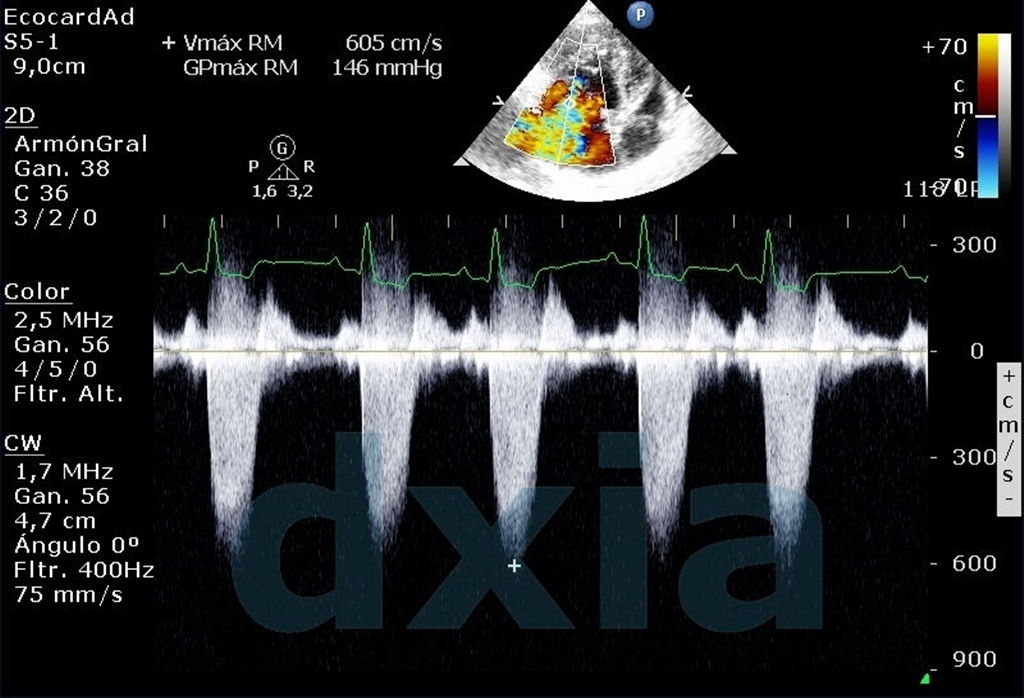

Utilizando los equipos de DXIA, estudiamos el corazón para detectar tanto patologías congénitas como adquiridas.